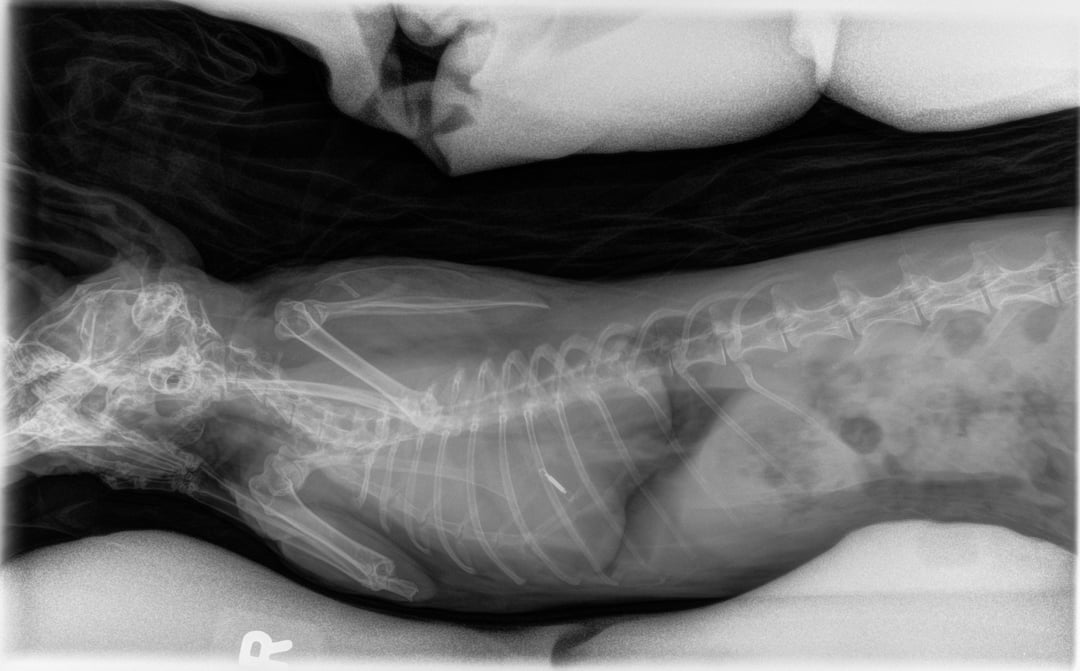

Hi everyone, our 6.5 year old girl, Hope, was recently found to have a mass in her chest on x-ray by our vet, which was performed after several months of coughing that didn't respond to antibiotics. Our vet and the radiologist believe it's a thymoma; vet didn't feel comfortable biopsying it due to risk but that seemed the most likely diagnosis. Apparently the most effective treatment is surgery and/or radiation, both of which are not options for us in our area. The vet recommended oral Prednisone to help slow the progression.